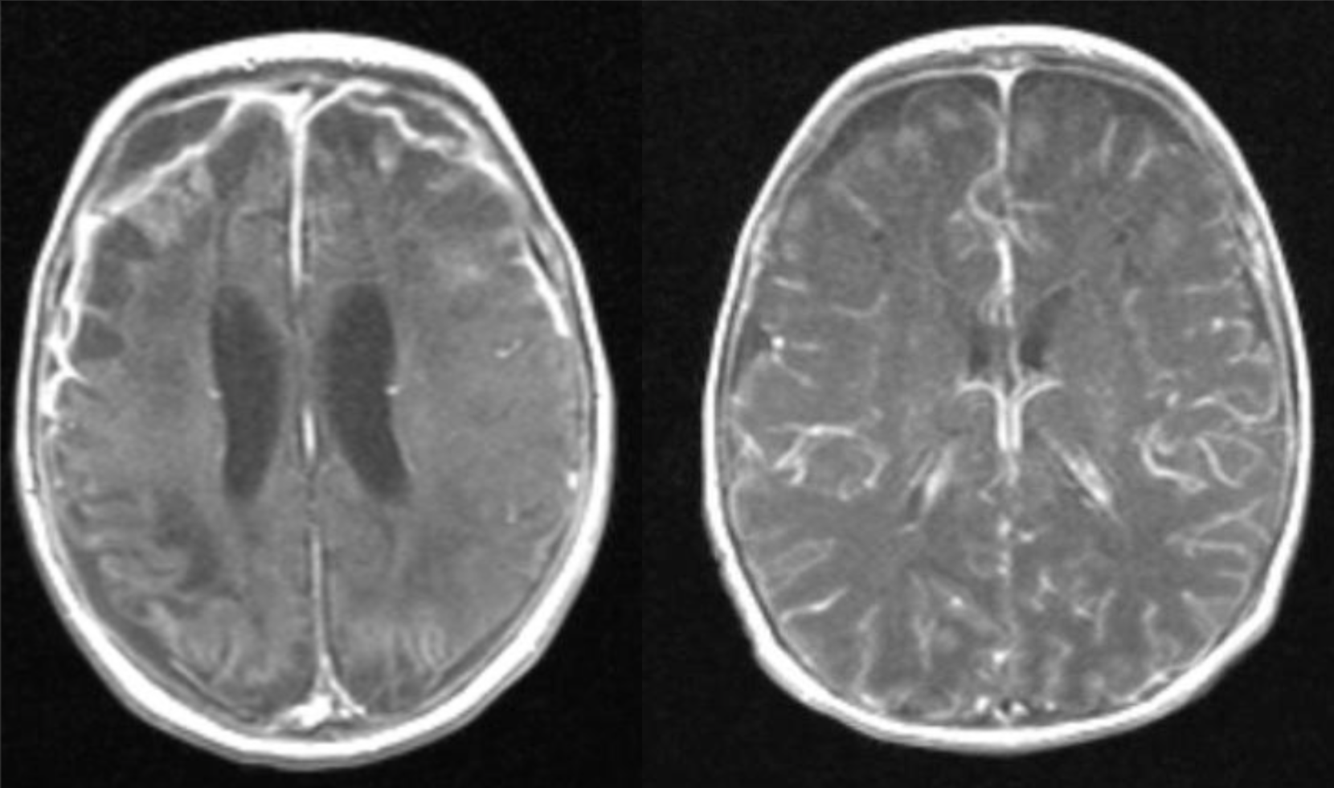

A 45 year-old man with untreated HIV infection presented with 4 months of cognitive slowing.

HIV dementia

Imaging